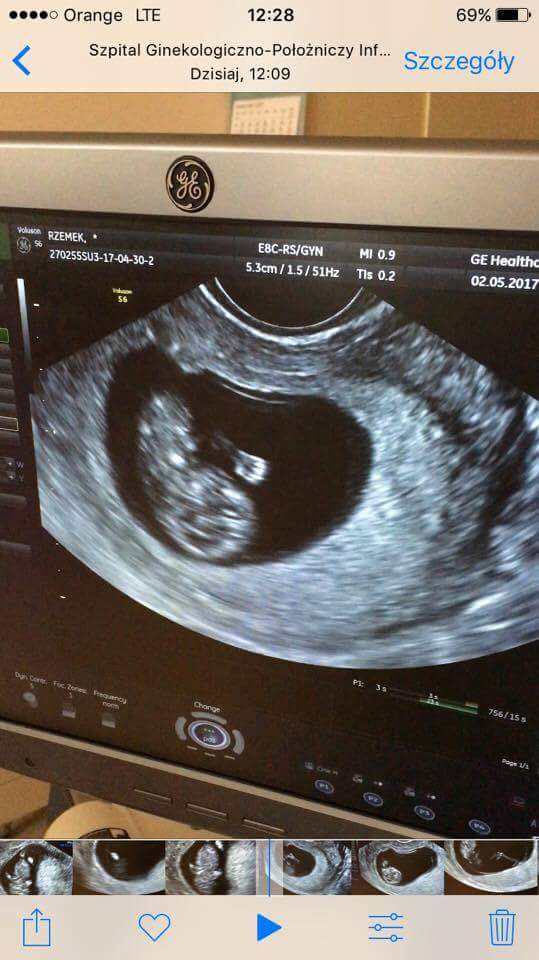

Super dzidzia gratulacje☺Zobacz załącznik 804782 Zobacz załącznik 804783 Zobacz załącznik 804784

My po wizycie

Na pierwszym zdjęciu widać rączkę, na drugim rączki, nóżki, na trzecim jest do góry nogami. Ruszał się, wręcz tańczył, serduszko tłucze jak szalone. Wszystko jest pięknie! Lekarz zachwycony, a my przeszczęśliwi![]()